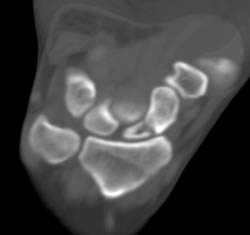

Scaphoid Fracture